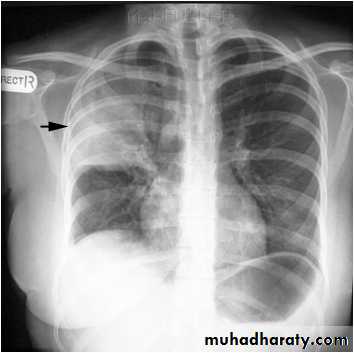

Right upper lobe consolidation

RUL consolidation will be seen as an increased opacity within the right upper lobe. Opacity may be sharply bordered by the horizontal fissureSome loss of outline of the upper right heart border may be apparent

Radiological sign in chest radiograph

Dense opacity seen above the horizontal fissure.

Air-bronchogram line

The lower border of the consolidation is sharply delinated by the horizontal fissure suggesting it lies in the anterior segment of the RUL